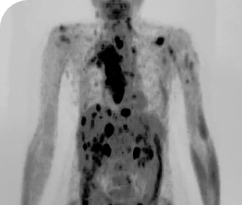

BASELINE

AFTER 31 MONTHS

33-YEAR-OLD MALE4

PATIENT CASE:

METASTATIC, RAIa-REFRACTORY,

PAPILLARY THYROID CANCER1,2

- 33-year-old male

- Progression on RAI and first line systemic therapy

- PRa after 2 cycles of VITRAKVI® (larotrectinib)

- Confirmed partial response on VITRAKVI lasting 55 cycles

Clinical presentation1

- Initially diagnosed at age 27

- Bulky disease in neck and thoracic involvement; metastatic, RAI-refractory papillary thyroid cancer

Prior treatments and outcomes1

- 5 prior surgeries

- 2 prior RAI treatments

- Systemic therapy with pazopanib and trametinib

Testing1,2

- ETV6a-NTRK3a gene fusion was detected during disease progression on systemic therapy via NGS

VITRAKVI treatment1

- VITRAKVI 100 mg twice daily orally

Response to VITRAKVI1,2

- Confirmed partial response (92.6% reduction in target lesions)

- Treatment continued for 55 cycles

- VITRAKVI was well tolerated; patient did not have to discontinue due to AEa

- No treatment interruptions or dose reductions

Response in primary and metastatic lesions1

Images courtesy of Dr Steven Waguespack.